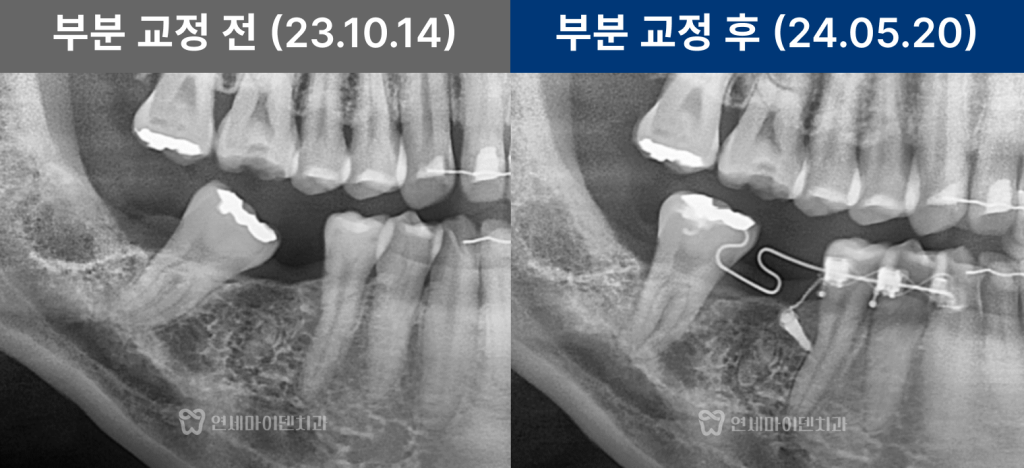

치아교정·임플란트 협진 케이스를 설명드리겠습니다.초진 상태

초진 파노라마 사진에서

오래전 6번 어금니가 발치된 상태였습니다.그 뒤쪽에 있던 7번, 그리고 사랑니가

앞쪽으로 상당히 많이 쓰러져 있었습니다.

원래 6번과 7번은

크기가 거의 비슷해야 하는데,쓰러지면서

임플란트가 들어가야 할 공간이

앞 치아보다도 더 좁아진 상태였습니다.이 상태에서 임플란트를 바로 진행하면

정밀한 힘 조절이 필요합니다.치아교정 7개월차: 공간 확보

약 7개월이 지나면서

쓰러졌던 7번 치아는 눈에 띄게 세워졌고

임플란트가 들어갈 수 있는 공간이

충분히 확보되었습니다.물론 더 이상적인 위치까지

완벽하게 이동시키는 것도 가능했지만,치아 뿌리 이동 범위와

치료 기간을 고려해

교합에 무리가 없는 선에서

효율적으로 마무리하는 전략을 선택했습니다.

목표로 해야 합니다.임플란트 식립과 마무리

공간 확보 후

임플란트를 정확한 위치에 식립했습니다.임플란트가 뼈와 안정적으로 결합되는 동안

교정을 병행해 공간을 유지했고,최종적으로 교합 간섭 없이

자연스러운 씹는 기능을 회복했습니다.

교정 전과 비교하면

임플란트 공간은 체감상 두 배 이상 확보되었고

다른 치아들의 불필요한 이동 없이

치료가 안정적으로 종료되었습니다.협진이 중요한 이유